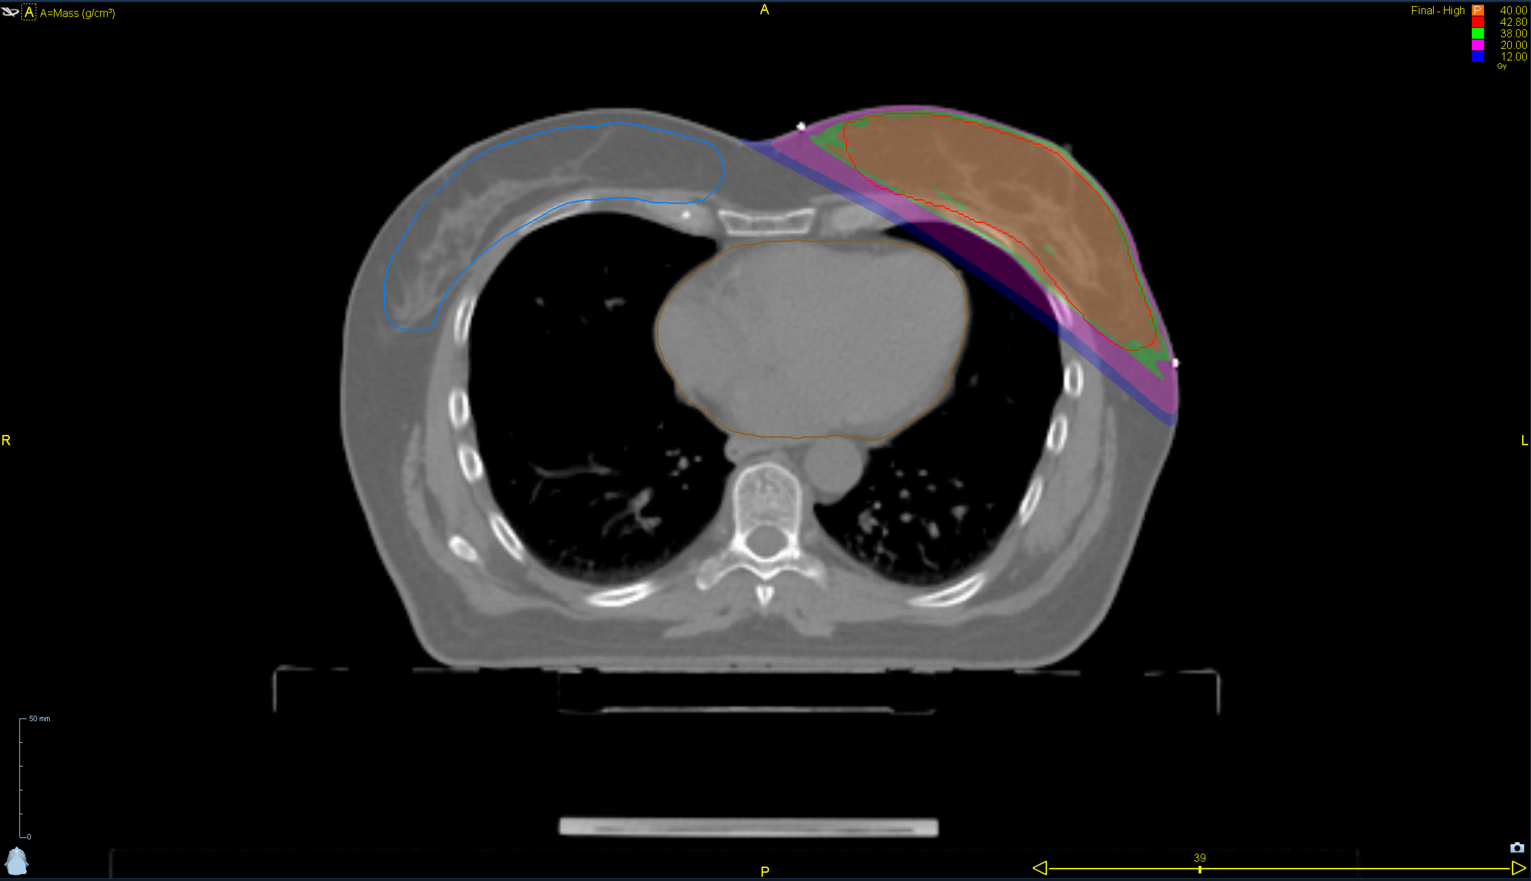

< View All Plan Studies RADIXACT SYSTEM TMI Case History AGE: 76-year-oldGENDER: Male Medical History Immidiate tolerance: Grade II dermatitis with eyelid edema, Grade I conjunctivitis resolved with Sterdex Diagnosis: Squamous cell carcinoma of the right lower eyelid Planning CT Images Treatment Plan Images ClearRT® Images Treatment Planning Highlights Fractionation